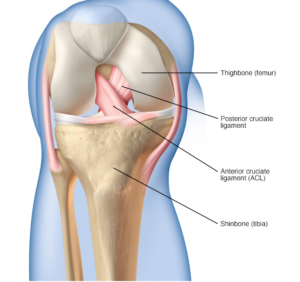

The anterior cruciate ligament (ACL) is a 3-4cm long band of fibrous tissue that connects the femur (thigh bone) to the tibia (shin bone). It helps stabilise the knee joint when performing twisting actions. The cruciate ligament is usually not required for normal daily living activities, however, it is essential in controlling the rotation forces developed during side stepping, pivoting and landing from a jump.

In the surgery a graft will be harvested to use to reconstruct the torn ligament. Usually two of the hamstring tendons are taken, but sometimes other suitable graft choices are used. This will be discussed with you prior to the operation. The remnants of the torn ACL are removed with keyhole surgery and tunnels are made in the tibia (shin bone) and femur (thigh bone) to allow the graft to be positioned across the knee. The new reconstructed ligament is then fixed at both ends to secure it in place.